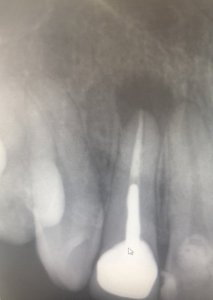

Около 3-х лет назад мне удалили нервы из верхней правой шестерки. Спустя 2 года воспалились корни, т.е. около 9 месяцев назад перелечивали корни, поставили коронку. Месяц назад зуб снова заболел, оказалось воспаление под корнем.

Хотелось бы узнать, действительно ли есть воспаление? И вообще в целом ситуацию насчет этого зуба, какое лечение следует предпринять? Есть 2 панорамных снимка.

Действительно, в зубе имеется хронический воспалительный процесс, причина — некачественное лечение каналов. Зуб будет лечиться в несколько посещений, и при квалифицированном подходе его вполне можно спасти.